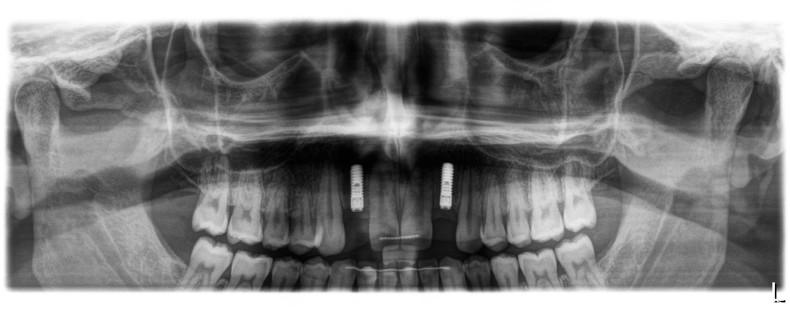

Ein 14-jähriger Patient wurde bei Aplasie der beiden oberen seitlichen Schneidezähne mit dem Ziel der beidseitigen Lückenöffnung kieferorthopädisch therapiert (Abb. 1a+b). Zum Ende der kieferorthopädischen Behandlung wurden zwei Miniimplantate in Regio 2er als temporärer Zahnersatz inseriert (Benefit System, PSM, 2 x 13 mm, Abb. 2a+b). Nach Abdrucknahme wurden Kronen auf den Peek-Abutments modelliert und diese mit Kunststoff auf die Abutments geklebt (Abb. 3a–d). In den Abbildungen 3 und 4 sind die klinischen und röntgenologischen Nachkontrollen innerhalb der nächsten achteinhalb Jahre dokumentiert. Man erkennt einen sowohl in der Höhe als auch in bukkopalatinalen Breite verbleibenden gesunden Knochen ohne Anzeichen einer Atrophie. Im Alter von 23 Jahren wurden die definitiven Implantate ohne die Notwendigkeit einer Augmentation eingesetzt (Abb. 5) und nach Einheilung prothetisch versorgt (Abb. 6a–e und Abb. 7a–c).